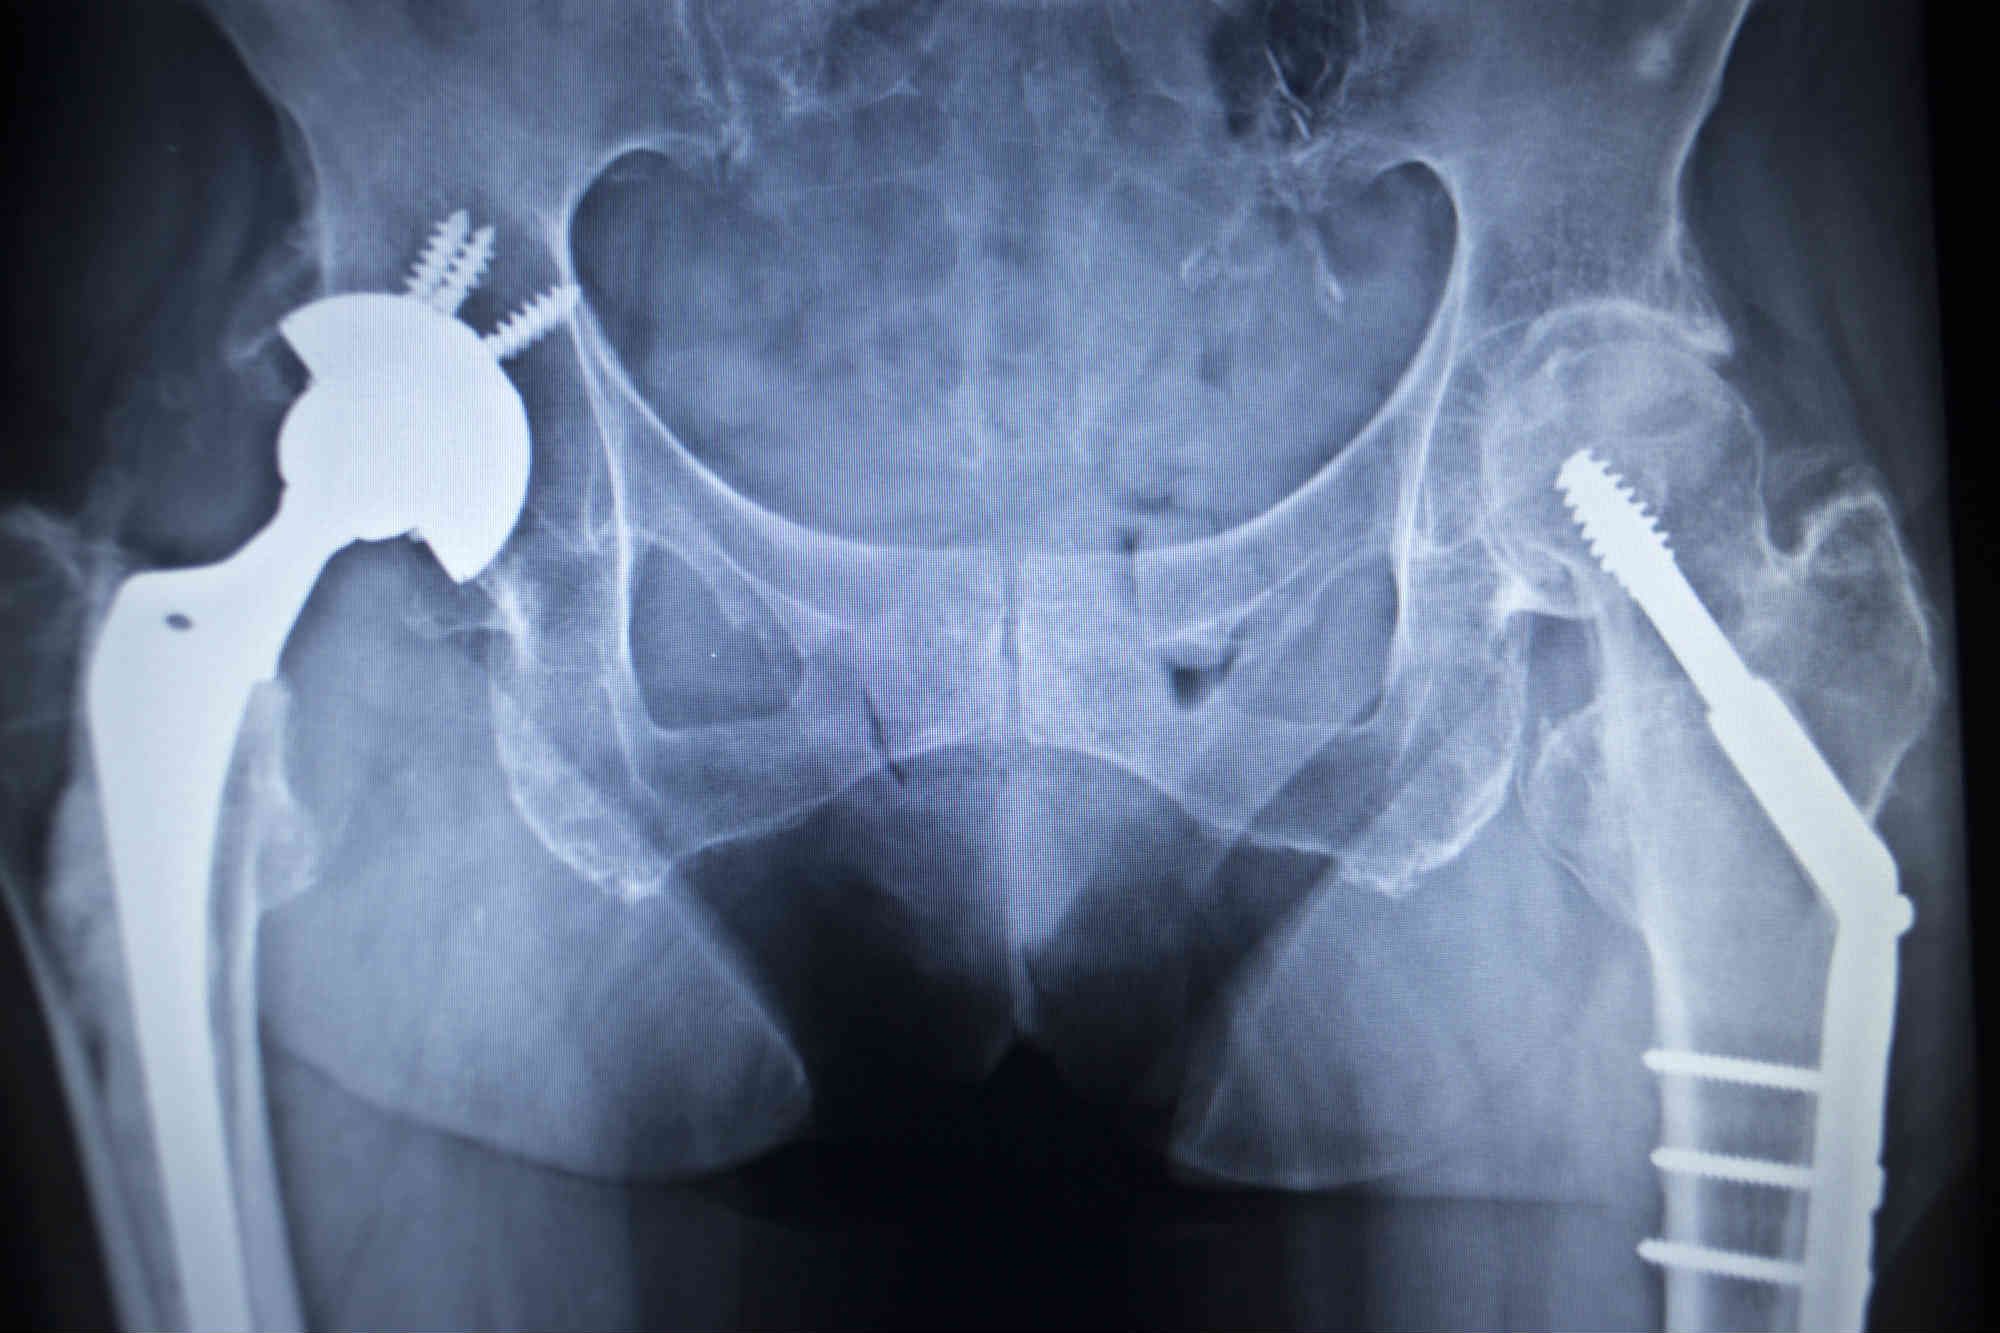

Stryker Hip System Failed Due to Defective Design, Patient Says

Used HOWMEDICA /STRYKER HIP OMEGA HIP SCREW SYSTEM. 3 SET OF HOWMEDICA Stryker Hip Replacement Surgical Technique The total system includes 12 body sizes ranging from size 0 to. The direct anterior approach can be used to implant a standard total hip prosthesis using instruments specially. Stryker mis technique for tha. The accolade ii femoral hip system is suitable for various surgical approaches, including direct anterior. One implant and instrument system that is designed to accommodate primary,. Stryker Hip Replacement Surgical Technique.

Stryker Hip Replacement Lawsuit Metal Poisoning & Dislocation Stryker Hip Replacement Surgical Technique The indications for use of the total hip replacement prostheses include: Minimally invasive surgery (mis) is a surgical technique, which may enable the surgeon to potentially. This surgical protocol is a guide to preparing the femur for an insignia hip stem. One implant and instrument system that is designed to accommodate primary, revision, and hip fracture cases. The total system. Stryker Hip Replacement Surgical Technique.